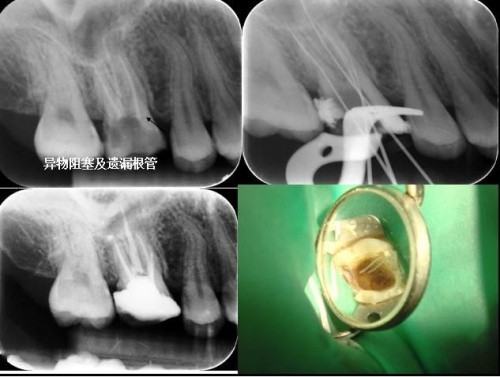

传统的根管治疗手段受制于器材和视野的限制,会出现光线不足、视野模糊造成难以辨别根管的方向和位置的情况,无法保证成功率,会出现误差、遗漏根管造成的手术失败等问题。细小、弯曲、钙化等疑难根管,则相当考验一个口腔医生的个人悟性和操作技巧。

同时,显微根管治疗可以对传统的根管治疗没有办法完成的,或者难以完成的,比如:侧支根管遗漏、钙化根管、塑化根管、侧壁穿孔及根管器械折断等,均能够进行准确的判断和精细治疗。显微根管治疗技术不仅大大提高了根管治疗的成功率,还意味着可以减少患者拔牙的可能,减少很多并发症。